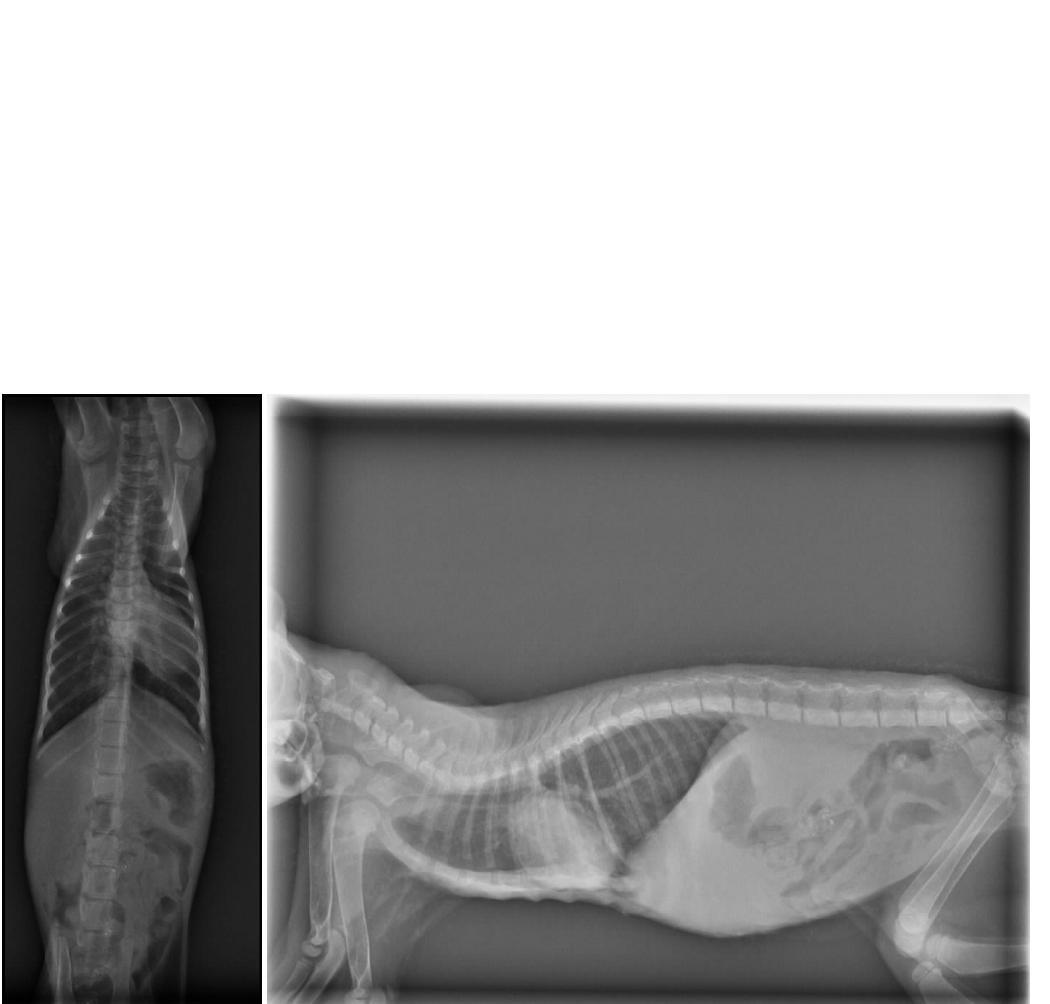

5)X-ray 400*2

哥哥

1)螢光染色 200

2)止痛眼藥水 200 (不折扣)

3)四環素眼藥膏 250 (不折扣)

4)血檢 1800+450+900

6)點滴抗生素治療 600*8

7)住院費用 400*8

8)除蚤 250(不折扣)

9)全營養靜脈輸液點滴 500*2 (不折扣)

10)噴霧治療 150*8

小計:13350*0.7+1700 = 11045